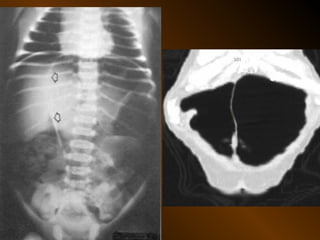

CĂNG GIÃN ỐNG TIÊU HÓA

• Căng giãn dạ dày

• Căng giãn tá tràng

• Căng giãn ruột non

• Căng giãn đại tràng

• Căng giãn ruột non lẫn đại tràng

PHÂN BIỆT

RUỘT NON – ĐẠI TRÀNG

• Các nếp Kerckring

• Nếp ngấn thanh mạc

• Khẩu kính

• Số lượng quai

• Phân bố các quai ruột

• Cao / rộng

• Chất cặn bã